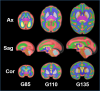

This is a multi-modal MRI (T2W and DTI) brain templates of fetal monkeys with atlas labels at three key time points over the second and third trimesters of the 168 day gestational term.. Specifically, template images are constructed for brains at gestational ages of 85 days (G85, N=18, 9 females), 110 days (G110, N=10, 7 females) and 135 days (G135, N=16, 7 females). T2W templates were able to characterize the development of fetal tissue zones and gyrification in cerebral cortex and DTI templates were able to infer the morphogenesis of cortical neurons and maturation of white matter tracts.